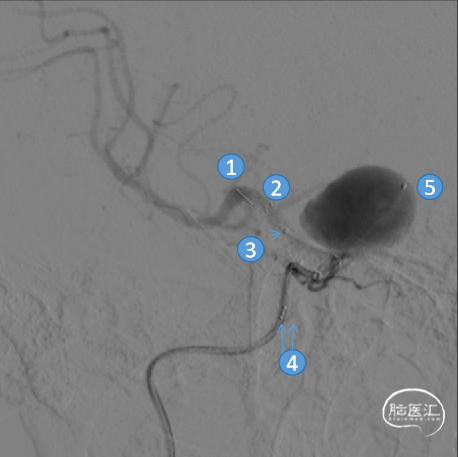

术中DSA造影:右侧颈内动脉正、侧位造影,显示右侧颈内动脉床突旁大型动脉瘤。

术中DSA造影:右侧颈内动脉3D造影提示:右侧颈内动脉床突旁大型动脉瘤,大小约为20.72×16.33mm,远端血管直径1.92mm,近端血管直径3.48mm。

通路建立:6F中间导管抵达颈内动脉海绵窦段后弯处,微导管在微导丝的配合下采用瘤内成袢及解袢技术,将微导管送至动脉瘤远端,手推造影远端血管无夹层及出血改变。

Headway™ 27 156cm微导管内输送FRED 4017血流导向密网支架,系统远端定位于预计着陆区以远2-3mm处,回撤微导管原位释放支架。释放至动脉瘤颈的迂曲处时,先回撤系统将微导管头端从大弯侧缓慢拉回至血管中央,观察到支架自膨打开后,轻推支架以保证支架贴壁。

①输送导丝头端

②支架远端显影点

③支架微导管头端

④输送导丝尾端显影点

⑤弹簧圈微导管头端